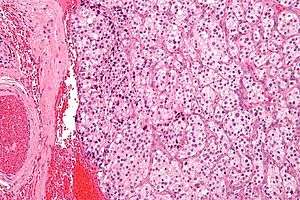

On microscopic inspection, the tumor cells are readily recognized. Individual tumor cells are polygonal to oval and are arranged in distinctive cell balls, called Zellballen.[3] These cell balls are separated by fibrovascular stroma and surrounded by sustentacular cells.

By light microscopy, the differential diagnosis includes related neuroendocrine tumors, such as carcinoid tumor, neuroendocrine carcinoma, and medullary carcinoma of the thyroid.

With immunohistochemistry, the chief cells located in the cell balls are positive for chromogranin, synaptophysin, neuron specific enolase, serotonin, neurofilament and Neural cell adhesion molecule; they are S-100 protein negative. The sustentacular cells are S-100 positive and focally positive for glial fibrillary acidic protein. By histochemistry, the paraganglioma cells are argyrophilic, periodic acid Schiff negative, mucicarmine negative, and argentaffin negative.

Micrograph of a carotid body tumor.